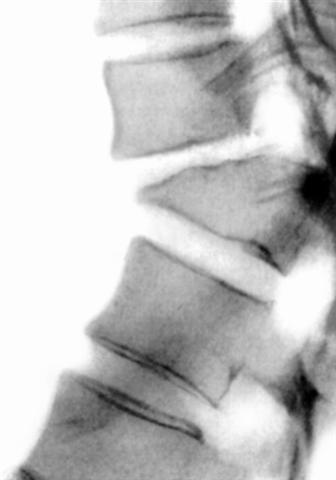

Рис. 10в). Рентгенограмма поясничного отдела позвоночника (боковая проекция) при компрессионном переломе с тяжелой степенью компрессии.